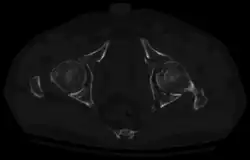

Axial CT image (viewed on bone windows) of a complex comminuted left acetabular fracture involving both anterior and posterior columns.

Axial CT image (viewed on bone windows) of a complex comminuted left acetabular fracture involving both anterior and posterior columns. -